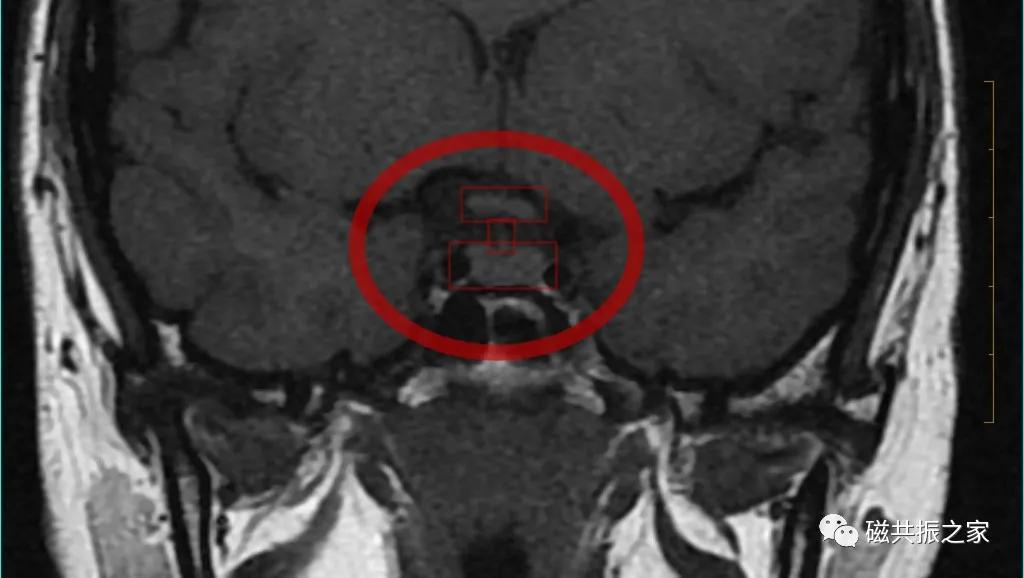

最理想的冠状位图像:同一层面视交叉、垂体柄和垂体均能清晰显示,共同组成“工”字结构。

冠状位是观察垂体柄形态和测量垂体高度最理想的方位。